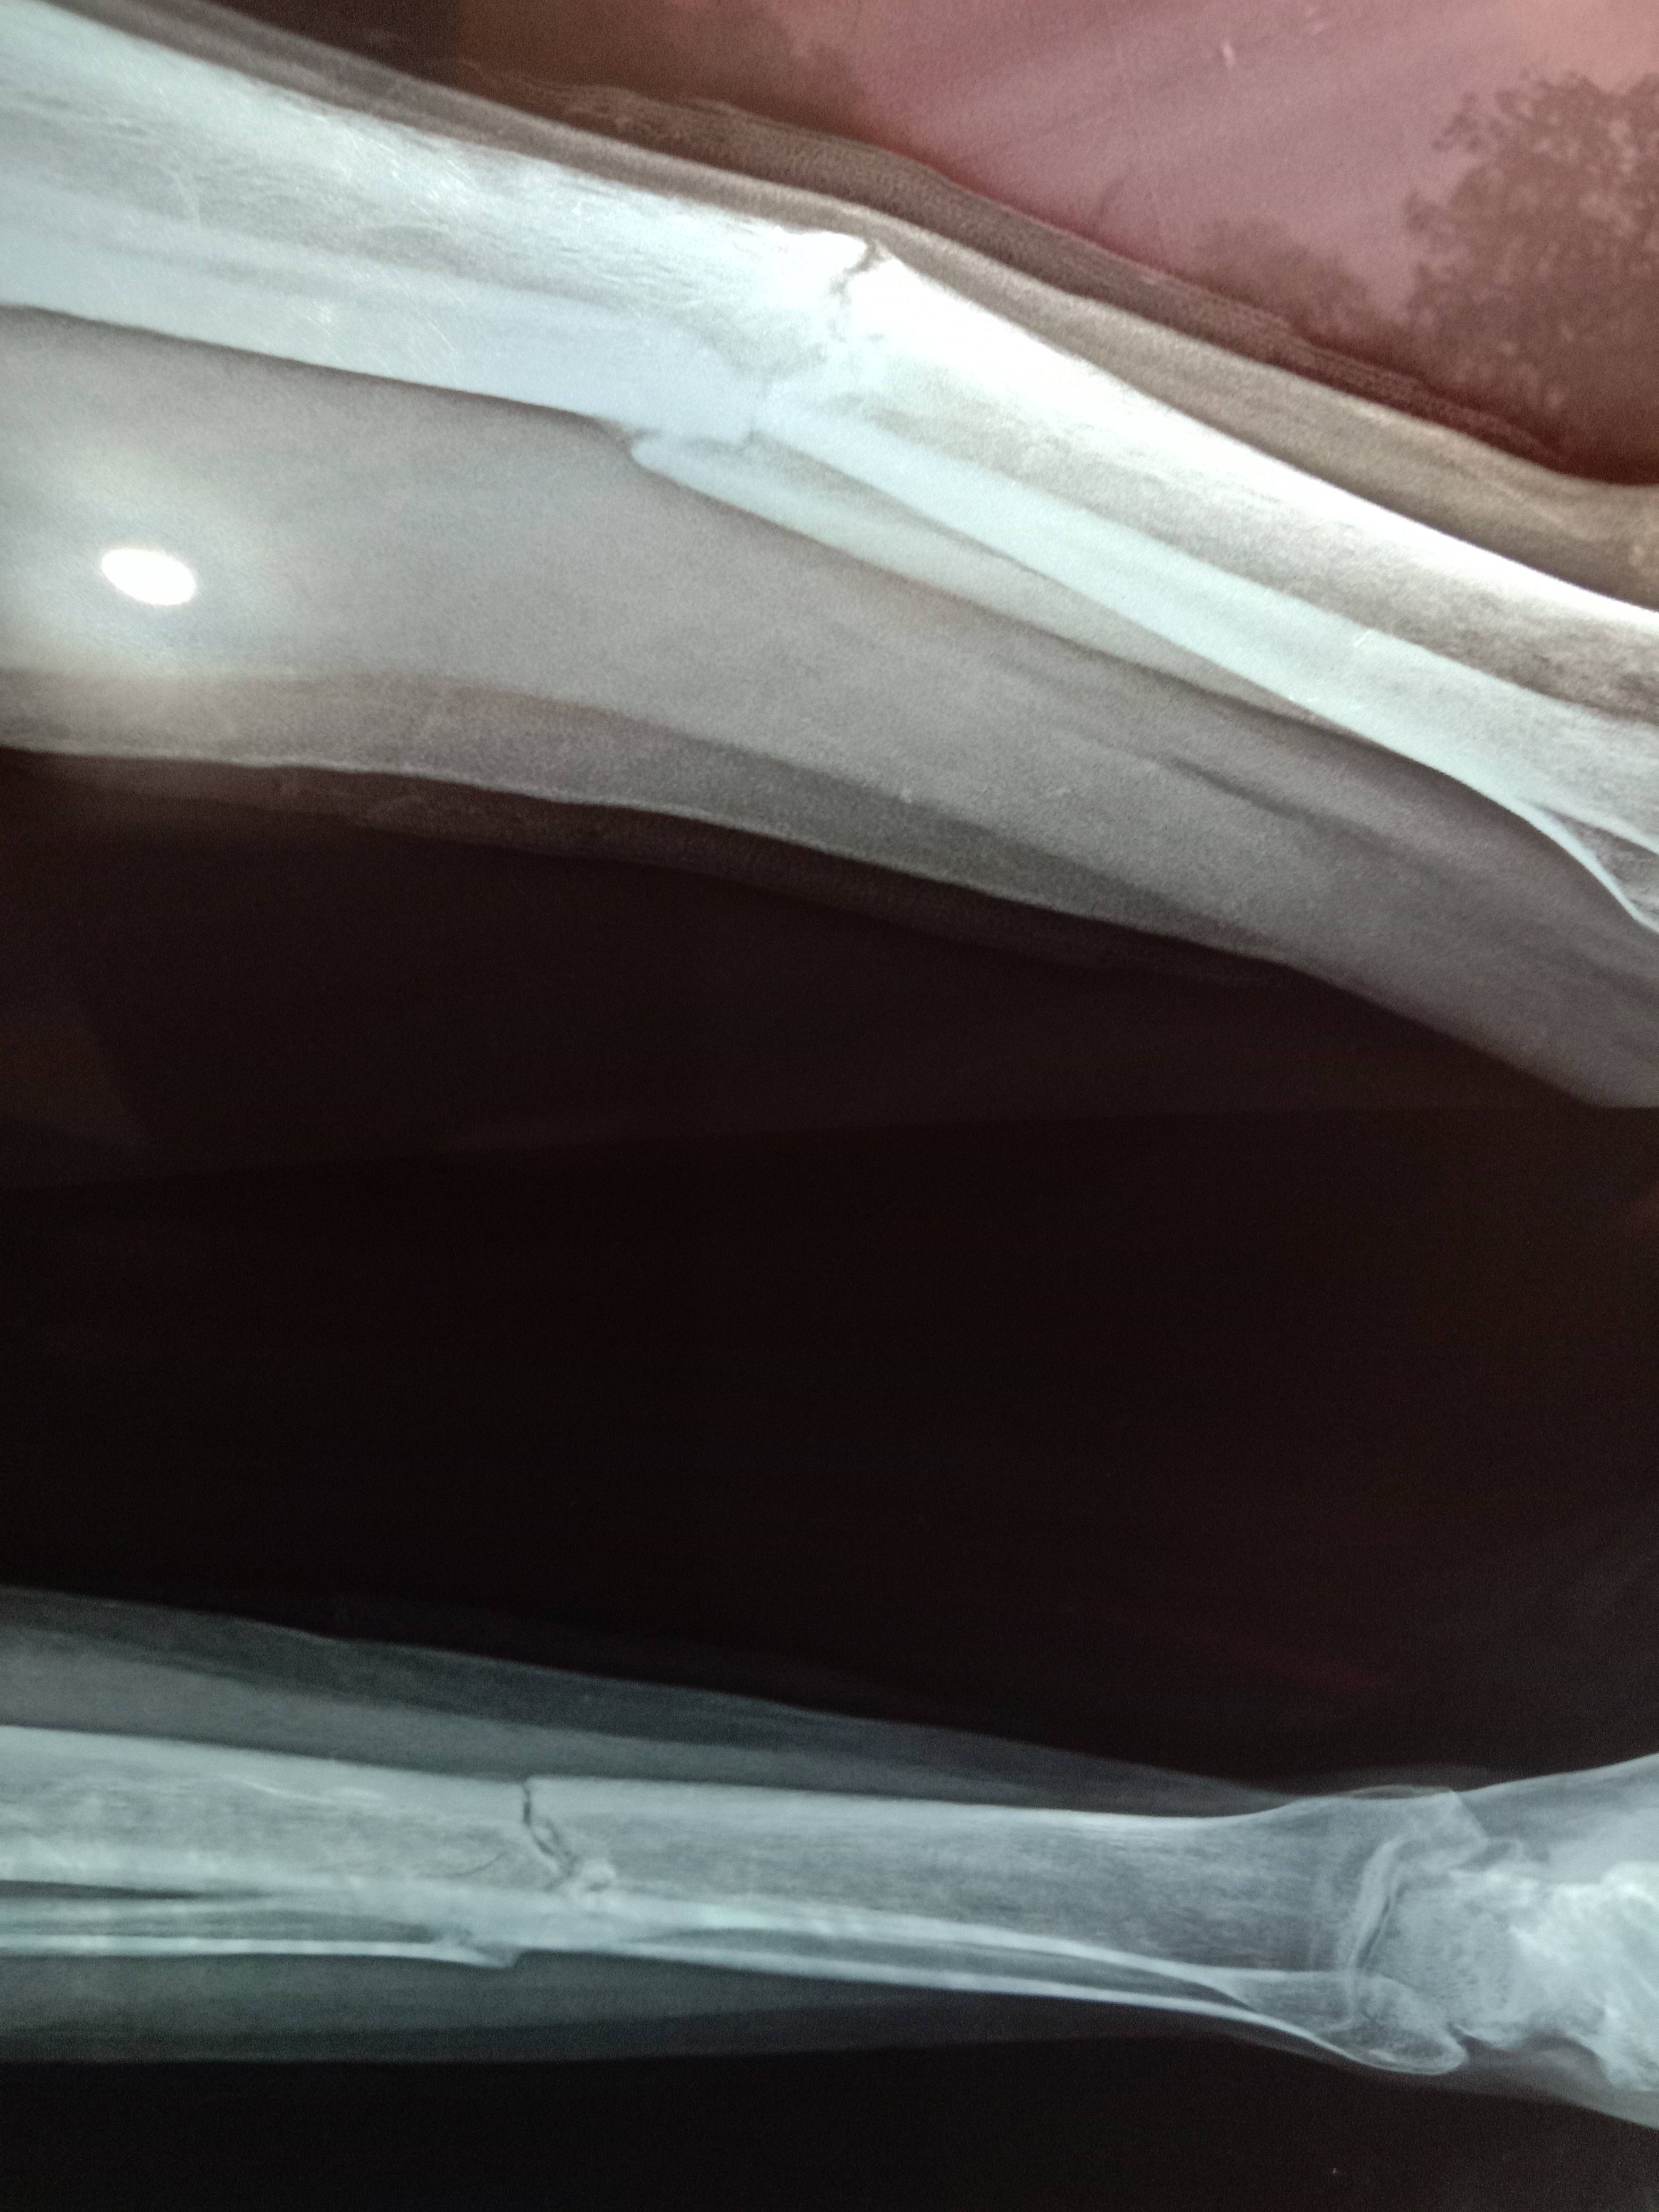

Sir this one is x ray after 5 month 11 days of surgery

will this bone unite or need bone grafting

Age only 20 years

ORIF has been done in this case